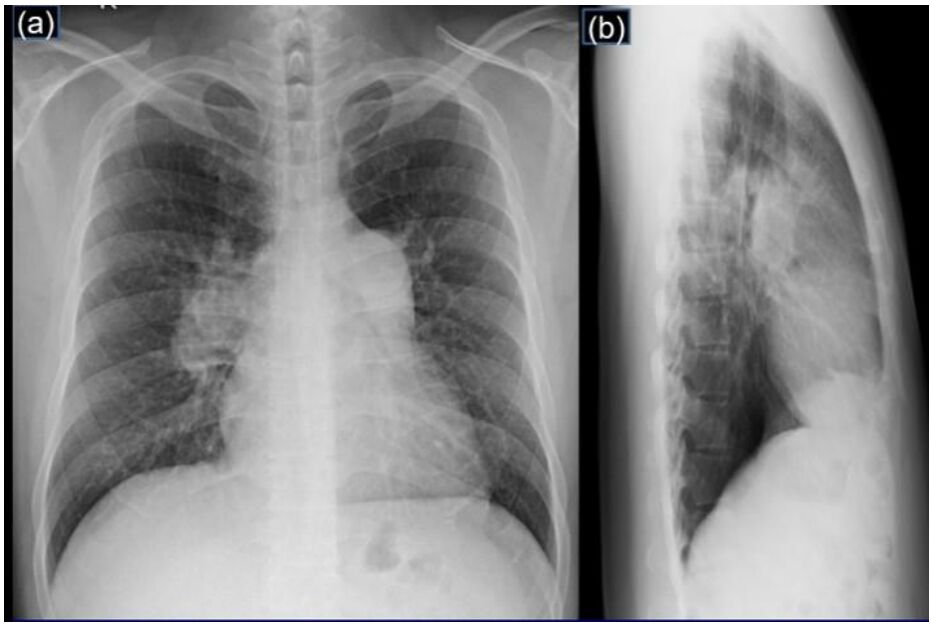

4. 病人是位29歲男性電子工程師派駐中國深圳,三個星期來,時有間歇性發燒及逐漸性呼吸困難,先在深圳 門診求醫,初以為一般感冒治療,後以支氣管炎診斷治療罔效,乃急回台灣求醫。經檢查,意識: E4M6V5; BP: 122/75 mmHg; PR: 116/min; RR: 21/min; Temperature: 37.6℃; SPO2: 94%(room air) 頸靜脈不怒張,未有貧血,胸部呈現瀰漫性濁音,心臟擴大,有Grade III/VI Diastolic murmurs at left upper sternal border,無肝脾腫大,無腹水。皮膚未有紅腫或出血斑點。2016/12/23心電圖及胸部X光如 圖。其血液、尿液及生化如次:Hemograms: WBC, 13.54(k/uL); RBC, 4.74(M/uL); Hb, 13.0 (gm%); HCT,40.2(%); MCV, 84.8 (fL); MCH,27.4(pg); Platelet,329 (k/uL); Seg, 81.5(%); Eos, 0.2(%)。尿檢: 正常。請 問這位年青病人的最可能診斷是: